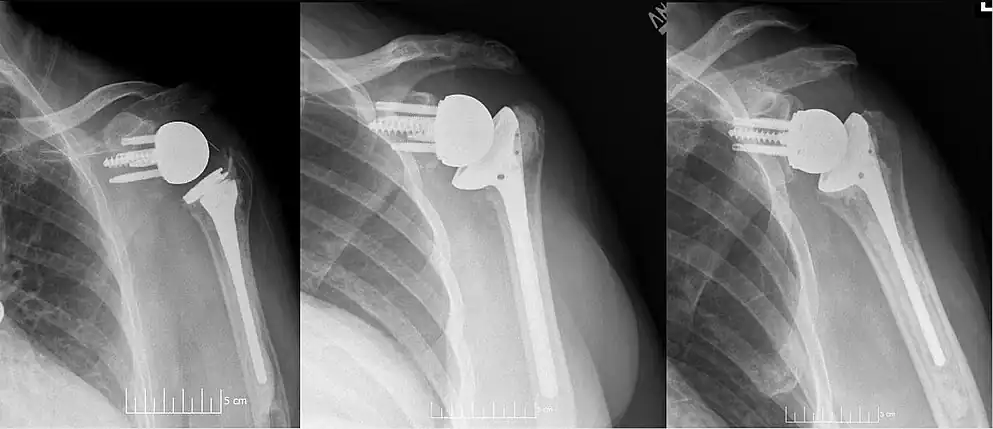

![]() Plain film radiograph in anteroposterior (AP) view of a right shoulder status post reverse shoulder arthroplasty using a prosthesis with a lateralized center of rotation. | |

Modern reverse shoulder implants consist of multiple parts. On the scapula bone, there is a metallic baseplate that grows into the bone of the native glenoid, screws and/or pegs that hold this in place, and a round metallic “glenosphere” component that is mated to the baseplate via several different mechanisms. On the humerus bone, there is typically a concave polyethylene liner that articulates with the convex glenosphere and is attached to a humeral stem that grows into the native humerus or is cemented into place. Within this basic structure there are multiple different variations of implants, and to date there is no consensus on which design is superior, although several studies have demonstrated some benefits to certain combinations.[10][11][12]